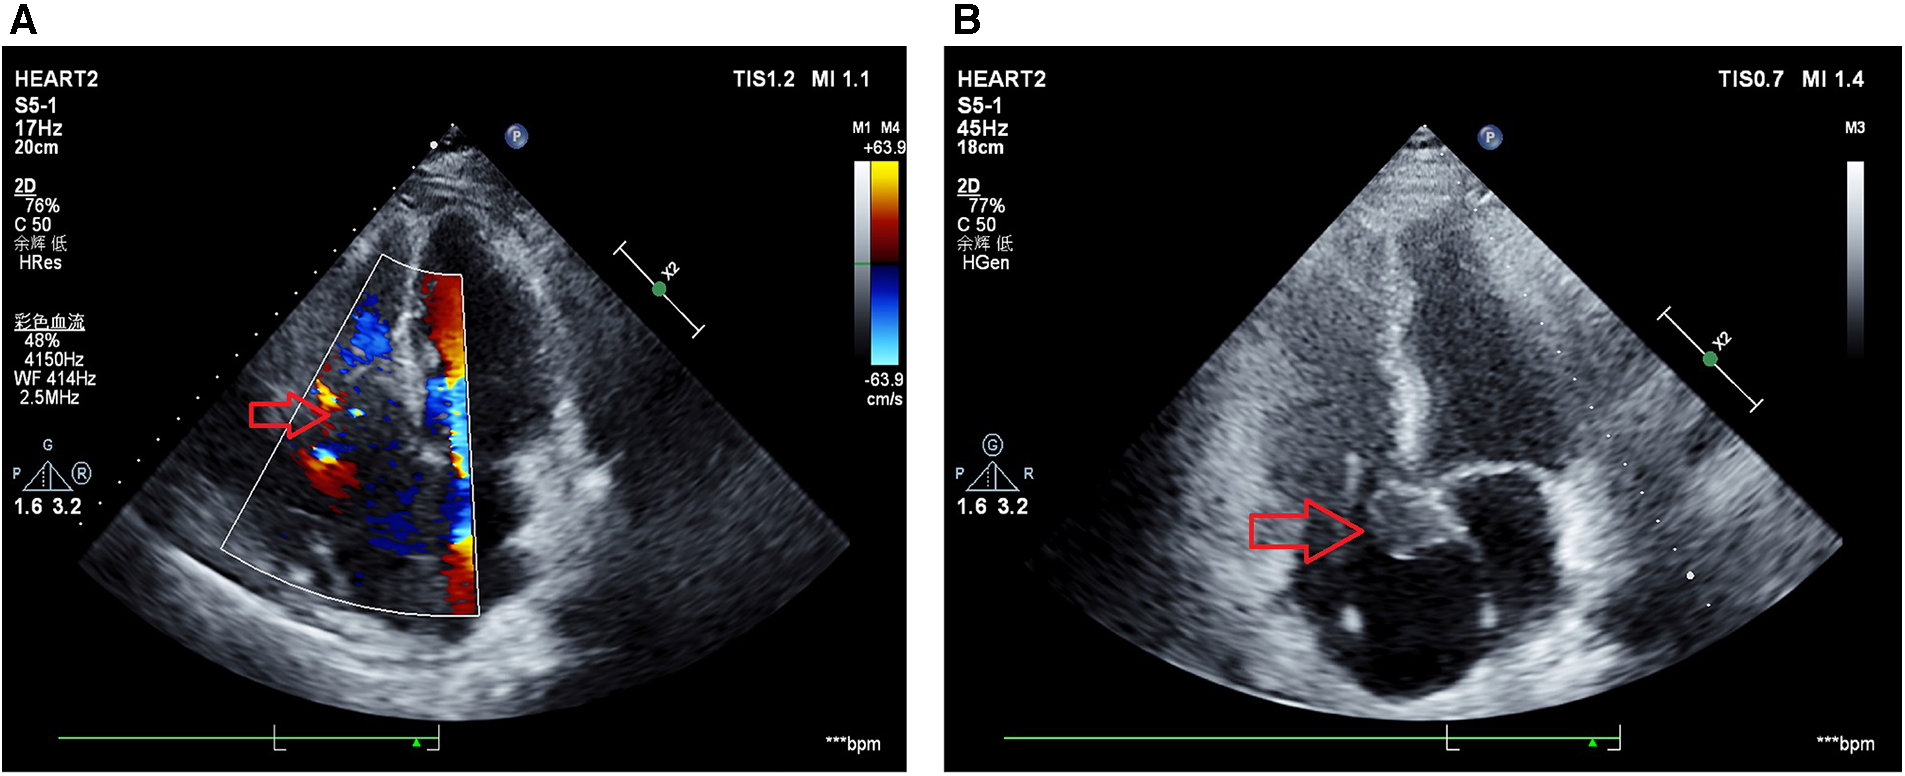

On October 19, 2022, echocardiography revealed an enlarged left atrium and a hypoechoic mass extending from the right atrium to the right ventricle with an irregular shape and a size of approximately 85 × 54 mm was (Figure 3A). The boundary between the mass and tricuspid septum was unclear, while the atrial septum was infiltrated by the mass, suggesting tumor recurrence and severe tricuspid stenosis. The patient was administered an rituximab, cyclophosphamide, doxorubicin, vincristine, and prednisone (R-CHOP) regimen. On November 1, 2022, echocardiography revealed the irregular shape of the right atrium, a solid mass measuring 25 × 21 mm, adhesion to the root of the tricuspid septum and lower atrial septum, enlargement of the left and right atria, widening of the aortic sinus, severe tricuspid regurgitation, and arrhythmia, with an ejection fraction of 71% (Figure 3B). Chest computed tomography showed exudation of the mediastinum and pericardium, slightly increased levels of blood and fluid, pneumonia, bilateral pleural effusion with atelectasis of the adjacent lung tissue, slightly narrowed left dorsal segment bronchus of the lower lobe of the lung due to compression, and aortic and coronary area calcification. Next-generation sequencing of the mass indicated a class I variation of CD79B (+), C.587A > C, which suggesting The adenine (A) at the 587th base position of the CD79B gene is replaced by cytosine (C). After three months post-surgery, the patient died due to severe lung infection following chemotherapy.

Figure 3

Echocardiography results after surgical resection. (A) Echocardiogram results at October 19, 2022 indicated a hypoechoic mass with irregular shape measuring approximately 85 mm × 54 mm is observed from the right atrium to the right ventricle. The boundary between the mass and the tricuspid valve is unclear, and the mass infiltrates the interatrial septum, suggesting tumor recurrence (with an increased size compared to pre-surgery) and severe tricuspid valve stenosis. (B) Echocardiogram results at November 1, 2022 indicated irregularly shaped solid mass in the right atrium, measuring 25 mm × 21 mm, adhering to the septal leaflet and inferior interatrial septum, with enlargement of the left and right atria, dilation of the aortic sinus, and severe tricuspid regurgitation.